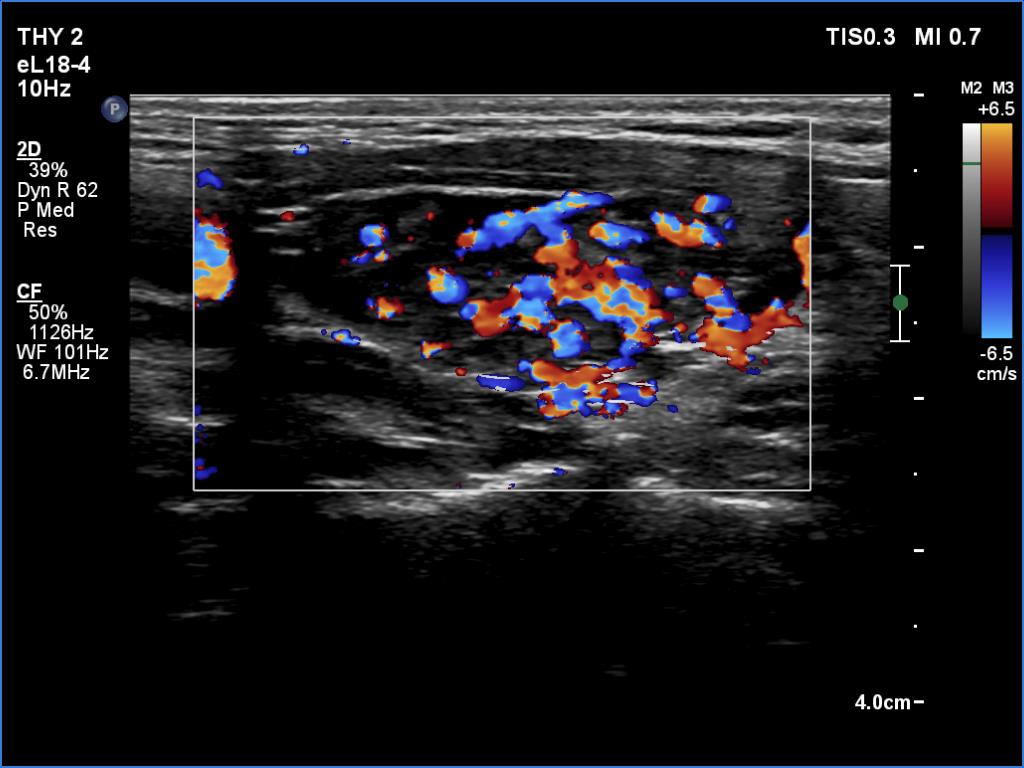

Ultrasonography. The thyroid was deeply hypoechoic and had numerous discrete iso/hyperechoic lesions. The latter had irregular shape and borders. The vascularity was increased. None of the discrete lesions corresponded to pathological nodules.